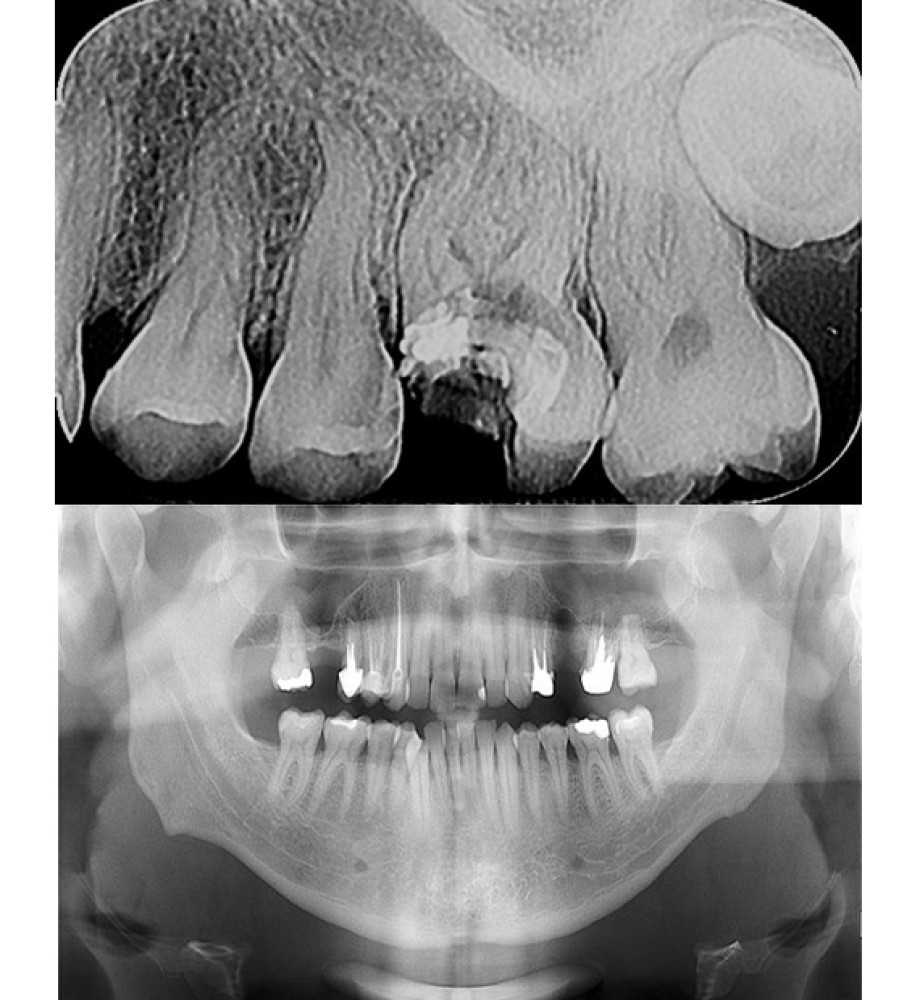

Digitalni dentalni radiogram ili retroalveolarni snimak zuba

Retroalveolarni snimci ili dentalni radiogrami, predstavljaju najinformativniju i najprecizniju vrstu snimka kada je u pitanju radiološka dijagnostika pojedinačnih zubnih regija. Ova vrsta snimanja može obuhvatiti najviše do četiri zubne regije u nizu (jedna pored druge) a minimalno dve susedne zubne regije, u zavisnosti od specifičnosti anatomije i patologije svakog pacijenta. Ova vrsta dijagnostike je najpouzdanija i nezaobilazna u dijagnostici upalnih procesa zubnih korenova, dijagnosike karijesa („zubnog kvara ili pokvarenih zuba“) provere punjenja zubnih korenova, provere posle plasiranja implanta i slično.